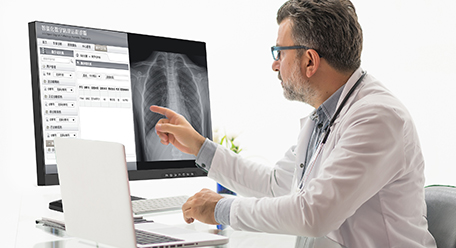

Monitor de radiodiagnóstico

Monitor de radiodiagnóstico

Áreas de aplicación: para sala de hacer la foto de radiología / sala de lectura / estación de imagen radiológica